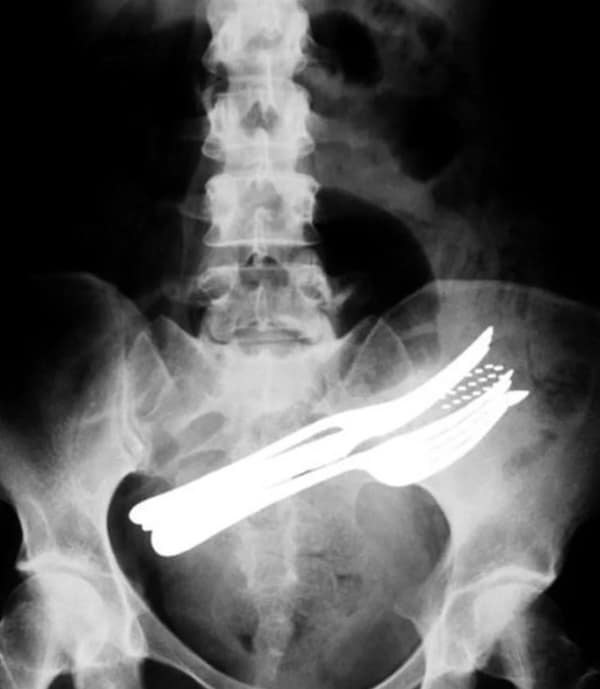

I used to think that nothing could surprise me anymore—until I stumbled upon some weird x-ray photos that made me reconsider my stance on human ingenuity (or lack thereof). Apparently, some people have a knack for getting objects lodged where they absolutely shouldn’t be. If you’ve ever wondered how not to use everyday items, these images might provide some unintended guidance.

This collection showcases 31 bizarre x-ray images that defy logic and anatomy textbooks alike. Each photo reveals unexpected objects making cameo appearances inside the human body, turning medical imaging into a gallery of the absurd. From common household items inexplicably found in unusual places to anomalies that would leave even seasoned doctors scratching their heads, these images offer a perplexing glimpse into the more “creative” side of medical emergencies. They highlight the intersection of curiosity, misadventure, and perhaps a dash of poor decision-making, all captured through the lens of radiology.